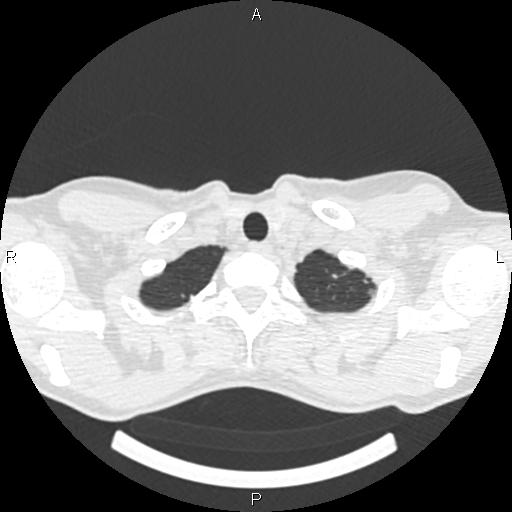

Женщина, 1975 г.р. ВИЧ инфицирована. Жалобы неспецифичны: легкое покашливание (иногда), легкое похудение. Температуры нет. Первое КТ сделано ровно 4 мес назад. Отмечались множественные...

Тип: Клиническое наблюдение

Область: Грудная клетка и верхние дыхательные пути

Модальность: КТ

Дата: 01.06.2016 - 20:47